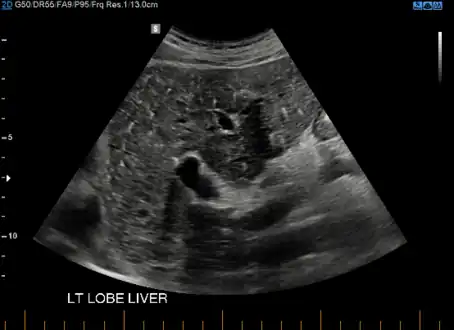

von Meyenburg Complex in ultrasound. Numerous little cysts with ringdown artefacts. von Meyenburg Complex in ultrasound. Numerous little cysts with ringdown artefacts.